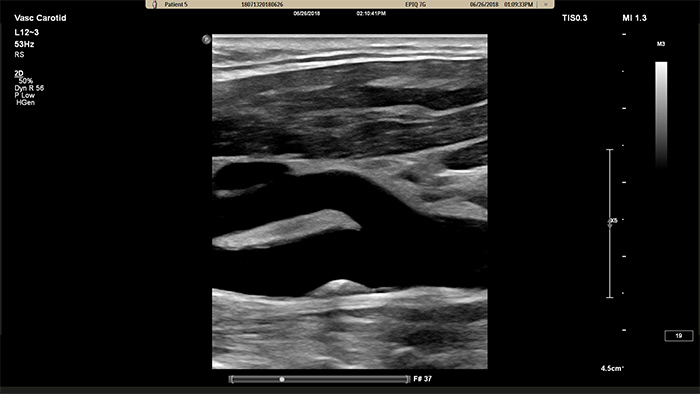

L'elaborazione di immagini di nuova generazione di Philips porta l'imaging vascolare a nuovi livelli, grazie alla capacità di delineare in modo eccezionale le interfacce dei vasi e fornire cospicuità avanzata della texture della placca. Riducendo l'offuscamento e gli artefatti dei vasi, XRES Pro aumenta l'affidabilità diagnostica dell'imaging vascolare dei pazienti, inclusi quelli tecnicamente difficili.